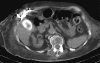

Spontaneous cholecystocutaneous fistula is a rare complication of chronic calculous cholecystitis because currently gallstones are diagnosed and treated at an early stage. This occurrence is possible even if it seems actually to be rare. We report the case of a 90-year-old woman admitted to our hospital with diarrhea of 4 days duration and low-grade fever (37.5°C). On physical examination, she had a 10 × 10 cm erythematous swelling and discomfort of the upper right abdominal quadrant; the skin and mucosae were dry. Transabdominal ultrasonography showed a gallbladder with abnormalities of the wall, a single gallstone impacted in the infundibulum and a fluid collection with irregular margins containing fluctuating echoes adjacent to the anterior abdominal wall of the upper right abdominal quadrant. A diagnosis of spontaneous cholecystocutaneous fistula with an abdominal purulent collection was reached. Due to the high anesthesiological risk of the patient, conservative management was carried out with fluids, broad-spectrum antibiotic, albumin and calcium supplementation. Computed tomography drainage of the purulent collection was also carried out. Both clinical and laboratory parameters substantially improved during the following two days, but on the third day of hospitalization, the patient died from a sudden arrhythmic event.